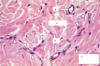

What type of cell is indicated by the black arrows? What does this type of cell do?

Type of cell: fibroblast

Activity: produces ECM fibers

What is the most common cell type in connective tissue?

fibroblast cells